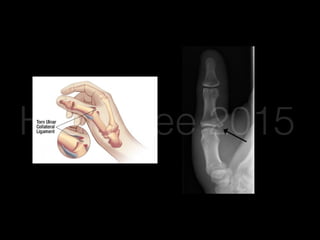

Skiier’s/Gamekeeper’s

Thumb

• Ulnar collateral ligament tear

• Forceful radial deviation of the thumb

• Pain, swelling on ulnar aspect of 1st MCP joint

• Valgus stress / radial deviation on 1st MCP with thumb

fully extended and in 30 degrees flexion

• Distal deviation >35 degrees or 15 degrees more than

unaffected thumb = complete tear